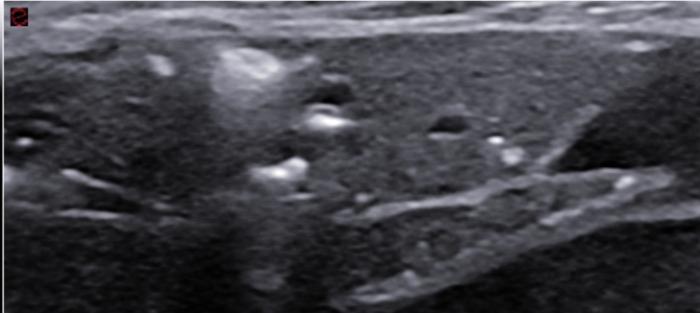

Signo tisular

Cuando la aireación se pierde por completo encontramos el signo tisular, en el cual podemos observar el tejido pulmonar conservado o no en su totalidad. A menudo se ha utilizado el término “hepatizado” para el pulmón que tras su falta de aireación se observa con un aspecto similar al tejido hepático (atelectásico) y el término consolidado se puede utilizar con más criterio para aquel que por un proceso infeccioso o neoplásico ha perdido su estructura normal. El signo tisular puede afectar a la totalidad de un lóbulo (Figura 13A.E).